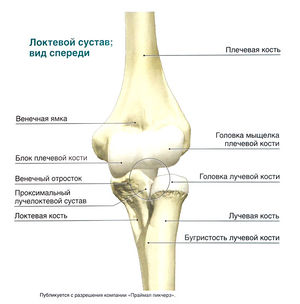

Локтевой сустав образован дистальным концом плечевой кости и проксимальным концом локтевой кости. Локтевая коллатеральная связка и лучевая коллатеральная связка ограничивают отклонение предплечья в стороны. Более подробно: Анатомия локтевого сустава

Пальпируемые анатомические ориентиры[править | править код]

Передняя поверхность

- Локтевая ямка

- Сухожилие двуглавой мышцы плеча

Медиальная поверхность

- Локтевой нерв

- Группа мышц, обеспечивающих сгибание и пронацию запястья

- Медиальный надмыщелок плечевой кости

- Локтевая коллатеральная связка

Латеральная поверхность

- Группа мышц, обеспечивающих разгибание и супинацию запястья

- Латеральный надмыщелок плечевой кости

- Лучевая коллатеральная связка